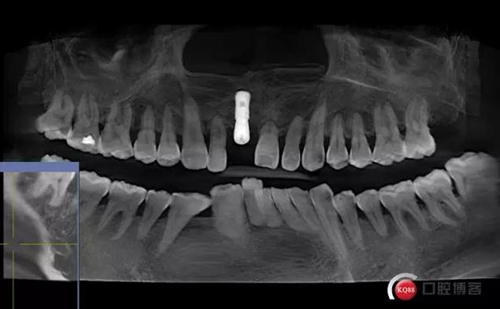

患者:王XX 年齡:42 上前牙松動(dòng)數(shù)年,從未做過(guò)任何處理,今來(lái)院就診;檢查:CBCT示上前牙區(qū)顎側(cè)一大小約7x7mm囊腫;治療計(jì)劃:即刻種植同期摘除囊腫

術(shù)后CBCT